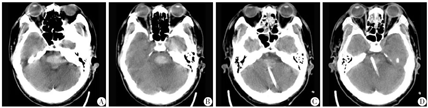

男性,50岁,主因"突发意识不清6 h"于2017年6月29日收治于解放军总医院第七医学中心神经外科。既往有高血压病史10年,未规律监测血压及服药控制。体检:血压200/100 mmHg(1 mmHg=0.133 kPa),神志深昏迷,GCS评分5分,双侧瞳孔圆形,直径约2 mm,对光反射迟钝,四肢肌力Ⅱ级,双侧巴氏征阳性。辅助检查:头颅CT示桥脑出血,出血量约8 mL(图1A~B)。初步诊断:脑干出血;高血压病3级,极高危组。入院后予以降压、止血等治疗,发病后15 h行无框架导航系统辅助下脑干血肿穿刺置管引流术。全身麻醉下,先仰卧位行气管切开术,然后右侧卧位,注册导航,穿刺点位于左侧横窦下2 cm,乙状窦和中线之间(图2A),根据导航指示设计穿刺路径(图2B~C)。术中切开头皮、皮下及肌肉层,颅骨钻孔,切开硬膜,调整无框架导航臂,置入带枕芯引流管,深度距小脑皮层约6 cm,拔出针芯,转动引流管同时以5 mL注射器缓慢轻抽出血肿约5 mL,缝合肌肉、皮下及头皮,固定引流管,术毕。术后2 d复查头颅CT提示引流管位置良好,血肿清除满意(图1C~D);头颅核磁DTI重建显示主要的神经纤维束得以保留(图3),拔除引流管。术后5 d患者清醒,恢复过程顺利,并发肺部感染,经抗感染治疗后好转,无消化道出血、中枢性高热等并发症,住院时间23 d,出院后行康复治疗。随访5个月,GOS评分4分。

A~B:术前CT提示脑干内血肿;C~D:术后CT提示引流管位置良好,血肿大部分清除